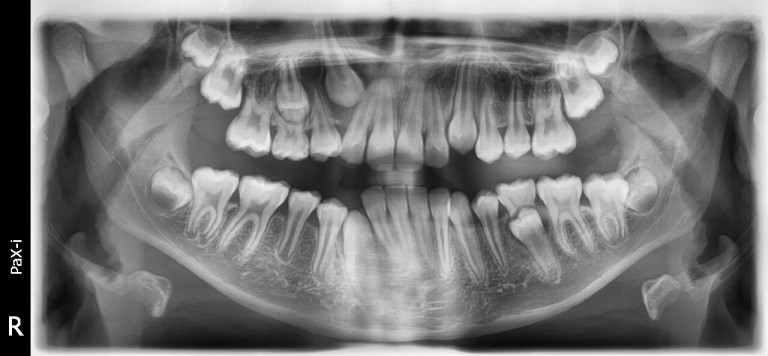

Zdjęcia panoramiczne i cefalometryczne.

Najnowocześniejszy cyfrowy aparat pantomograficzny Vatech Pax-i z przystawką cephalometryczną oraz techniką multifokalną , zapewnia najwyższą jakość zdjęć , potrzebnych do leczenia stomatologicznego i ortodontycznego.